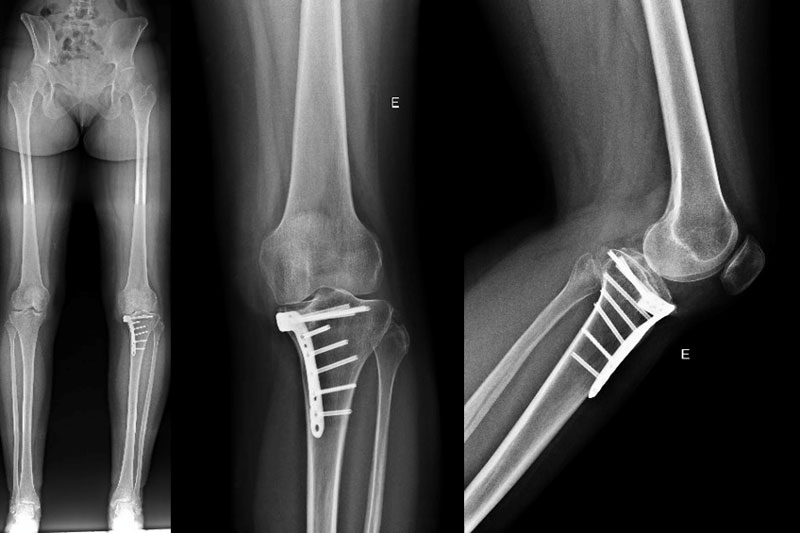

Post-operative X-rays

In this case, our choice was to perform a shiba osteotomy (intra-articular osteotomy) thanks to a custom-made cutting guide (NEWCLIP), and a PCL reconstruction thanks to a posterior tibial tendon allograft.